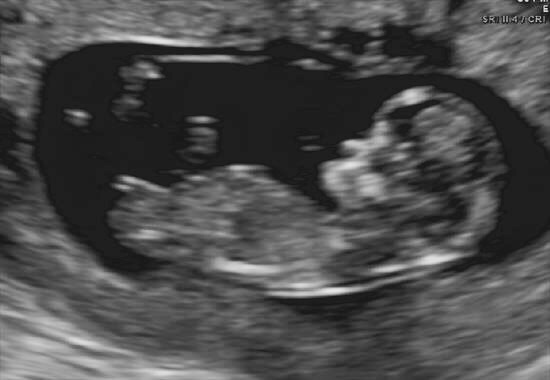

12 weeks 2 days!! Any nub guesses please would love as many as possible!!Attachment 28100